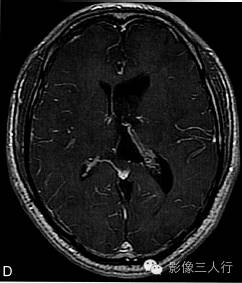

A.T2WI横断面;B.T1WI横断面;CFLAIR冠状面;D、E、F.增强横断面、矢状面、冠状面;G、H.CT平扫、增强;I.HE×100

肿瘤呈类圆形,边界清楚,位于左侧脑室前角及室间孔区,左侧脑室前角、三角部及左侧脑室后角扩张积水。MRI平扫T2WI(图A)肿瘤呈稍高信号,内见小范围高信号区;T1WI(图B)肿瘤呈等信号,内见低信号区;冠状面水抑制相(图C)肿瘤呈稍尚信号,内部原长T1长T2区信号呈低信号;增强扫描(图D~F)肿瘤强化不明显;CT平扫(图G)左侧脑室前角类圆形、边界清楚、较均匀等密度肿块,增强扫描(图H)强化不明显。

室管膜下瘤(subependymoma),也称为室管膜下室管膜瘤,亚室管膜瘤,室管膜下胶质瘤以及室管膜下星形细胞瘤等。为少见的缓慢生长的良性肿瘤,WHO分类属于室管膜肿瘤,I级,1945年由Scheinker首先发现并报道。该肿瘤组织学特征主要是由室管膜细胞和星形细胞构成。室管膜下瘤约占全部颅内肿瘤的0.2%~0.7%,可发生于任何年龄,大多在40~80岁,具有症状的常为小儿、年轻人,男性多见。室管膜下瘤生长缓慢,大多无明显症状,当肿瘤发生阻塞引起脑脊液循环障碍时,可出现相应的临床表现,头痛是室管膜下瘤最常见的临床表现,此外,还可出现头晕、呕吐等其他与网内压增高相关的症状和体征。本病可发生于脑室系统任何部位,主要见于4脑室及侧脑室,也可以发生于脑室系统外或旁的一些部位;侧脑室内室管膜下瘤靠近室间孔或透明隔。肿瘤边界清楚光滑、增强无或轻微强化是室管膜下瘤重要的影像学特征,也是鉴别诊断的重要依据。肿瘤CT平扫呈等密度,MRI T1WI为略低或等信号,T2WI为稍高信号,大部分侧脑室内肿瘤可见多发小囊变灶,增强扫描多无强化或轻微强化。本例诊断的关键在于观察肿瘤有无强化,室管膜下瘤无强化,从而可与脑室内其他肿瘤如室管膜瘤、胶质瘤及脑膜瘤等相鉴别。文献报道发生在4脑室内的室管膜下瘤钙化发生率较高,且增强扫描后不均匀强化,与室管膜瘤及其他脑室内肿瘤不易鉴别。与室管膜瘤不同,本病无侵袭性生长及沿脑脊液播散的特征,手术易完整切除,术后不易复发,预后较好。